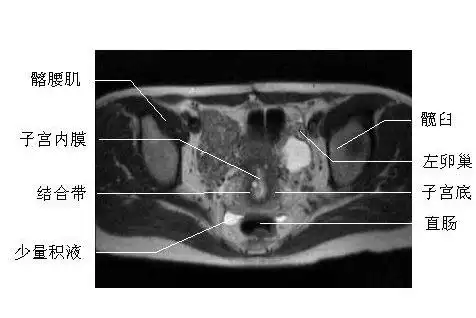

盆腔mri断层解剖你掌握了吗

子宫的磁共振图像

女性盆腔横断面mri图片